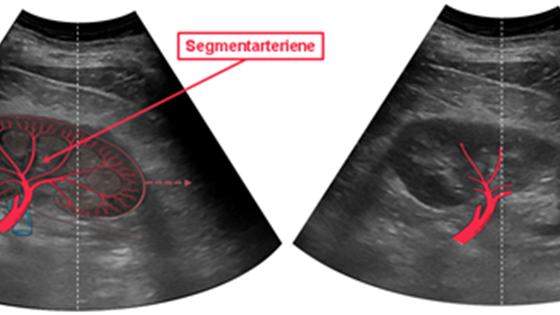

I prosjektet utvikler vi algoritmer for automatisk segmentering og tracking av nyrearterier i ultralydopptak ved hjelp av dyp læring.